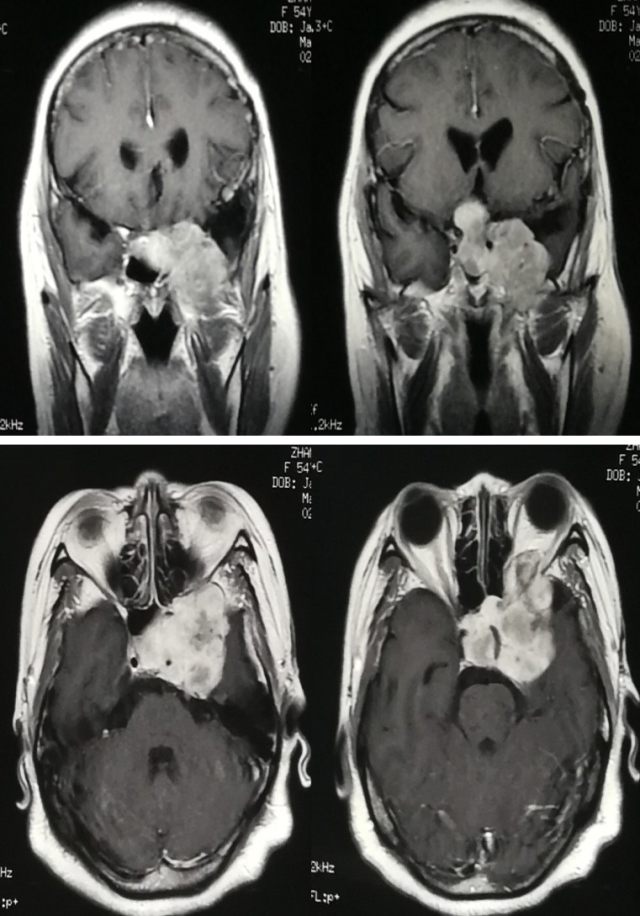

手术切除生长在颅颈交界区的颅底肿瘤比较困难,主要原因是该部位解剖复杂,肿瘤可能侵袭周围骨性结构并压迫或包绕脑干、椎基底动脉及分支和多组颅神经,术后容易发生颅颈交界区不稳定以及严重的脑干和其他重要结构的损伤。手术采用分阶段肿瘤切除联合后入路枕颈融合术提高颅颈交界区的稳定性,可显著提高肿瘤的全切除率,同时降低术后并发症,提高患者生活质量。